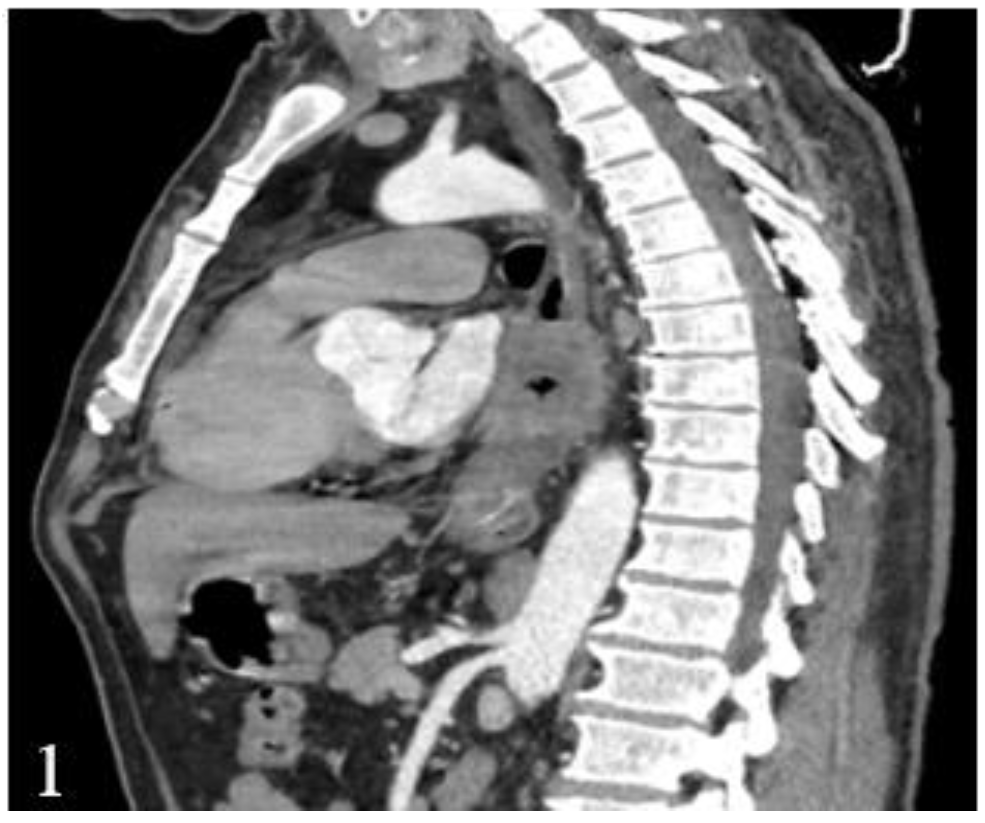

This finding has a major influence on the thoracotomy decision, which has to be taken not only based on computed tomography, due to the low diagnostic accuracy (Figure 1 and Figure 2).

Figure 1.

Postcontrast CT, arterial phase, sagittal plane. Circumferential marked parietal thickening of the distal thoracic esophagus and gastroesophageal junction with heterogeneous structure that generates stenosis.